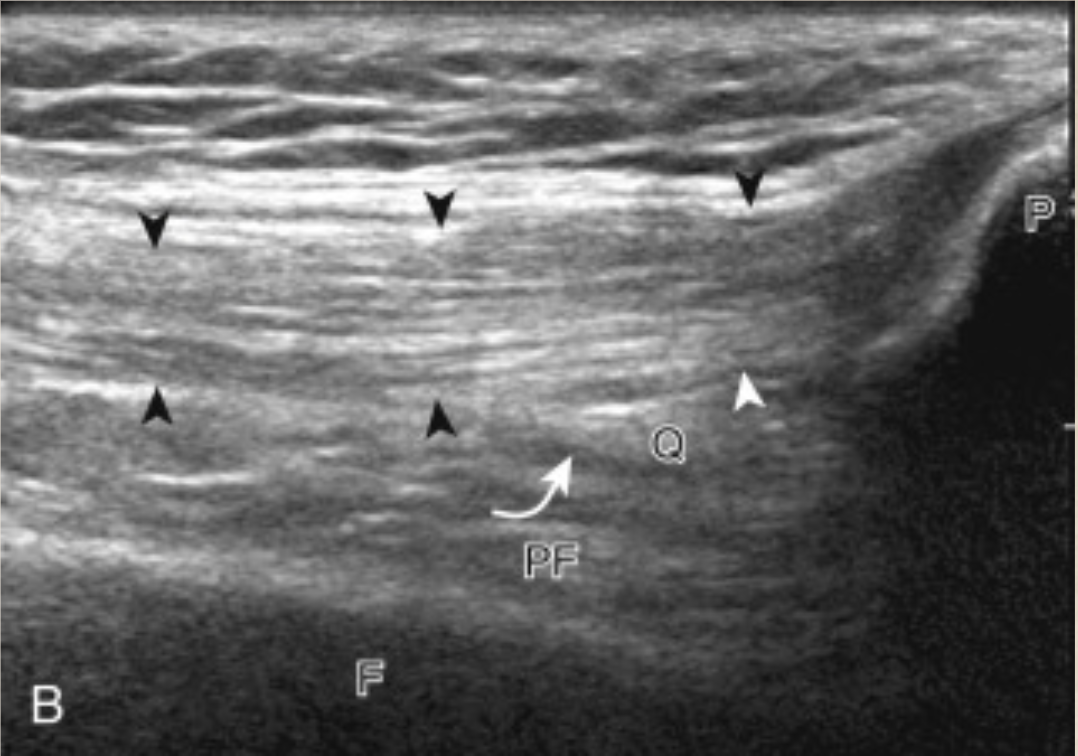

The arrows delineate the quadriceps tendon

F is femur

PF is prefemoral fat pad

Q is quadriceps fat pad